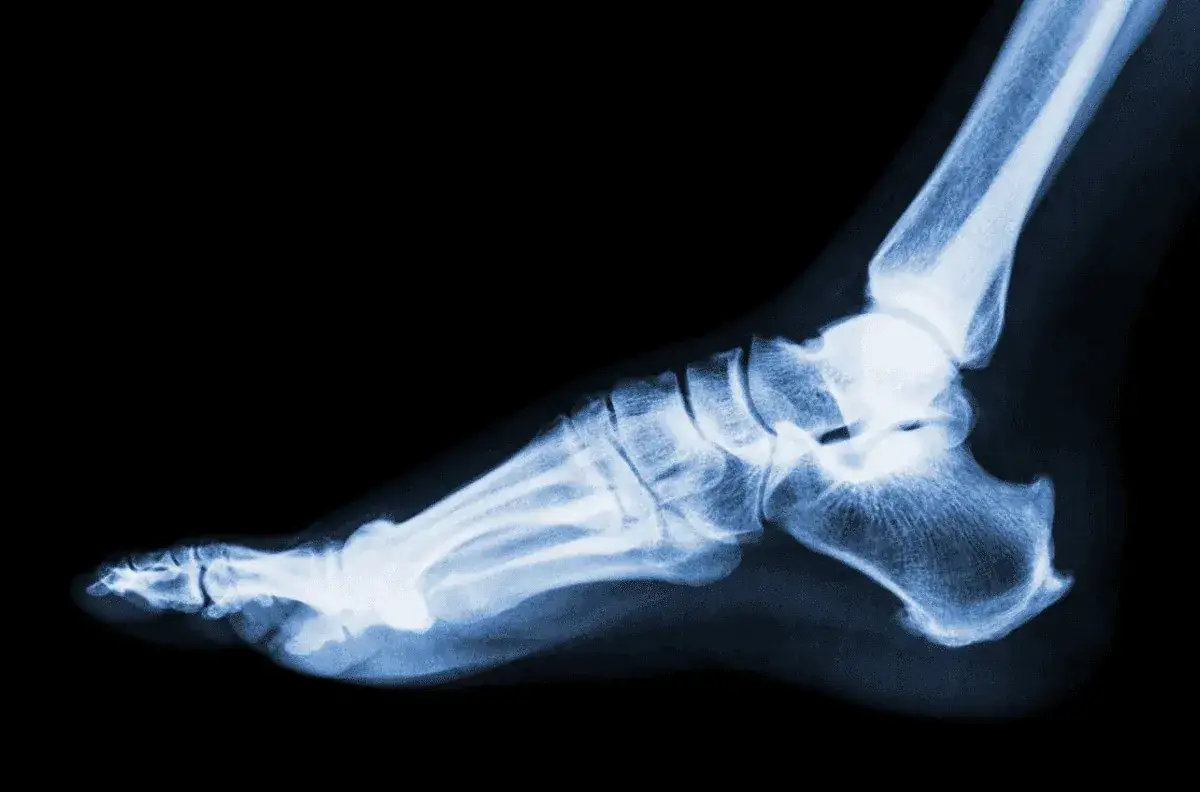

Czas potrzebny na powrót do zdrowia po skręceniu stawu skokowego jest ściśle powiązany ze stopniem uszkodzenia więzadeł. Rozróżniamy trzy główne stopnie urazu, z których każdy wiąże się z innym zakresem objawów i czasem rekonwalescencji.